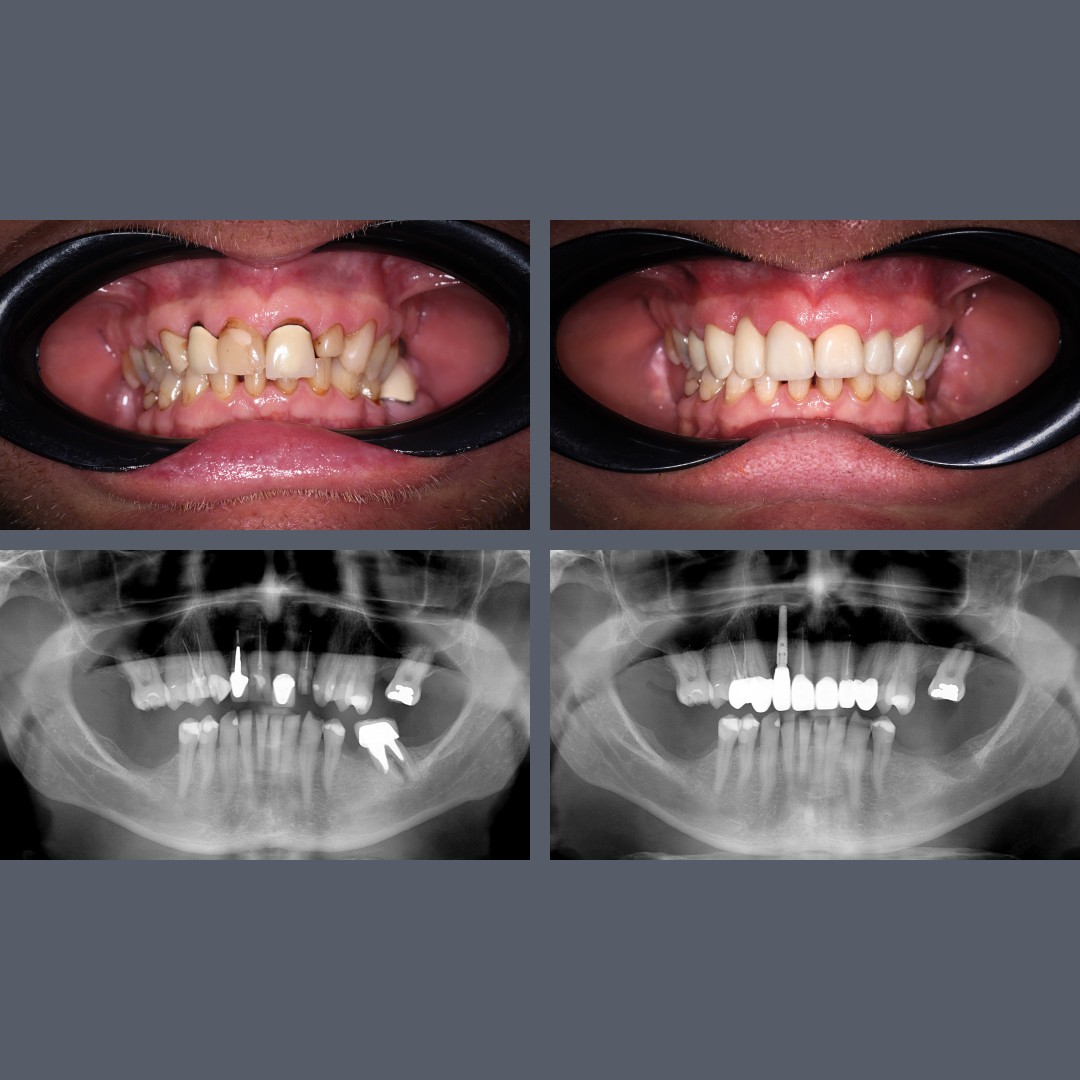

before-after

Upper All-on-4® and Lower Implant-Supported Crowns and Bridges – A Remarkable Smile Transformation

Treatment: ALL-ON-4®